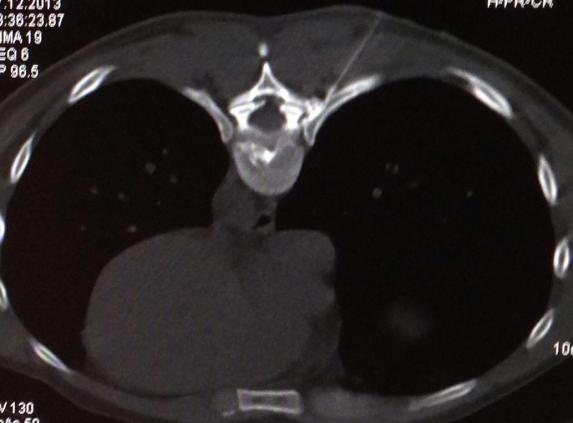

Die Komplikationsmöglichkeiten sind im Vergleich zur offenen Operation geringer, der Krankenhausaufenthalt beträgt maximal 1 Tag und die Arbeit kann zügiger wiederaufgenommen werden. Auch eine Vollnarkose ist nicht erforderlich.